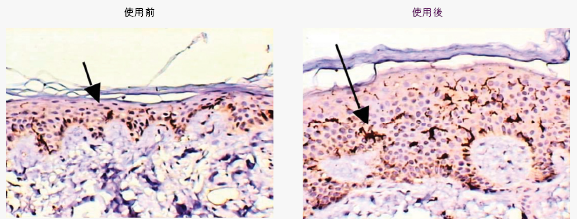

首先, CG210™ 制止細胞過早死亡並進入退行期,預防早期脫髮及維持頭髮生長。治療後,患者的頭皮部分表皮BCL-2+細胞(箭嘴)增加。